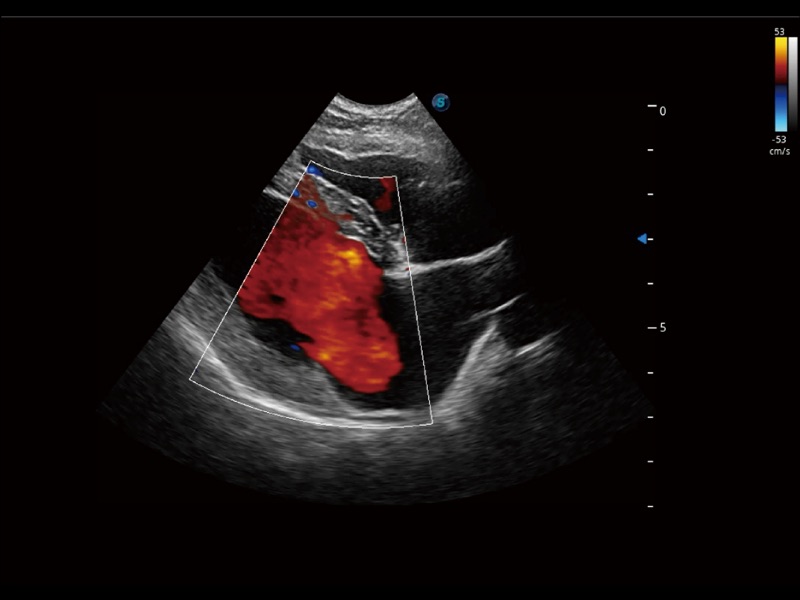

优异的基础图像

(犬)左室长轴血流